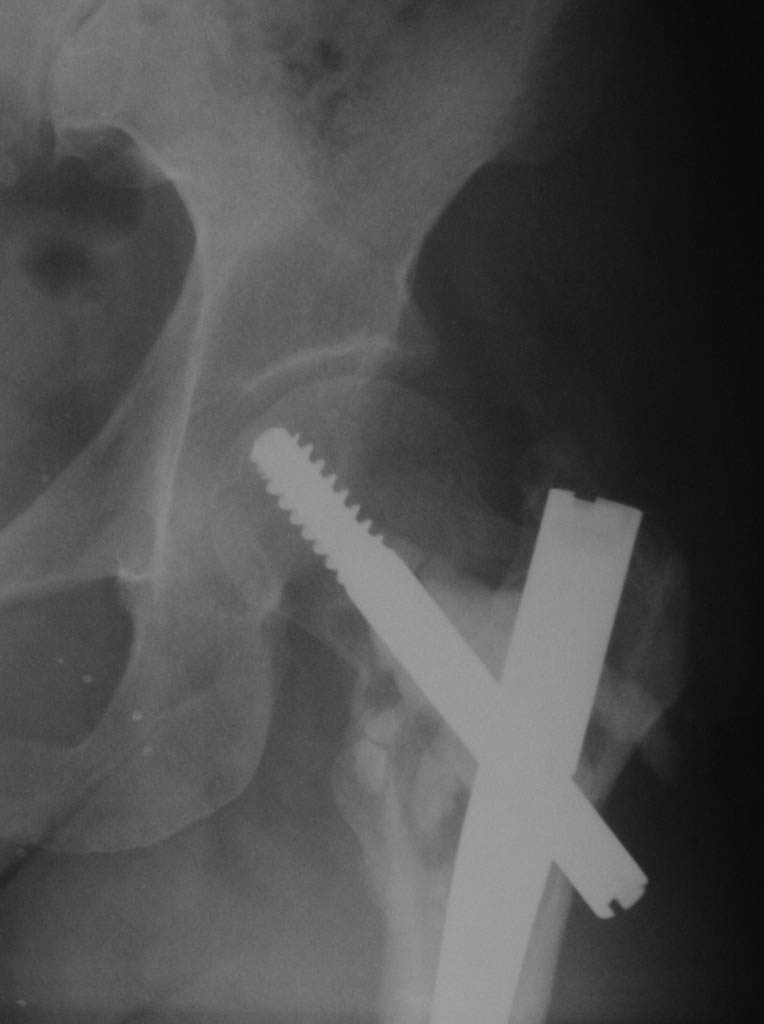

Добрый день. 2,5 месяца назад пациентке по поводу патологического чрезвертельного перелома правой бедренной кости (киста) был выполнена закрытая репозиция и БИОС гамма-гвоздем Stryker с заполнением полости Hydroset.

Гистологическое заключение: участки остеонекроза,хроническое воспаление. На этой неделе больная обратилась с жалобами на боли в области левого тазобедренного сустава. Со стороны оперированной ноги жалоб нет. Проведенное рентгенобследование выявило наличие полостного образования в проксимальном метадиафизе левой бедренной кости, перелом наружной стенки. Планируем выполнить БИОСлевой бедренной кости по методике аналогичной на правой ноге и этому случаю Какой фиксатор выбрать: длинную гамму или универсальный бедренный гвоздь?